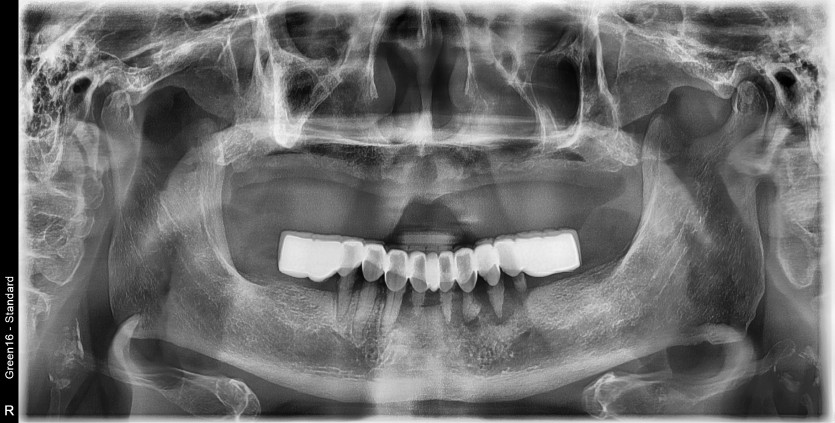

만 82세 하악 풀아치 증례

하악 풀아치 증례입니다.

6개의 임플란트로 완성하였습니다.